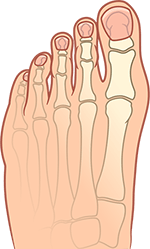

Mi az a bütyök?

deformált ízület

normál

A Hallux valgus a leggyakoribb ortopédiai betegség. A nagylábujjak csontjain dudorok formájában jelentkező kellemetlen és fájdalmas deformációk jellemzik.

A hallux valgus tünetei:

kiálló nagylábujj ízület

a láb gyors fáradása

a lábfej elülső részének lapossá válása

fájdalom szindróma járás vagy hosszadalmas állás után

a nagylábujj többi ujj felé dőlése

duzzanat és bőrpír a deformált ízület területén

a többi lábujj deformációja